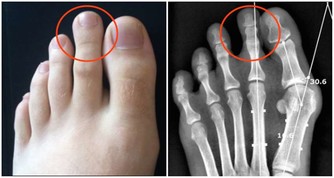

此外,有一些碳酸飲料如可樂會加入磷酸。如果長期攝入超過人體正常需要2-3倍的磷,則會使鈣的代謝出現變化,導致鈣大量流失,還會造成鈣離子在腎臟中和尿液中某些物質反應,形成不溶物,最終形成腎結石。